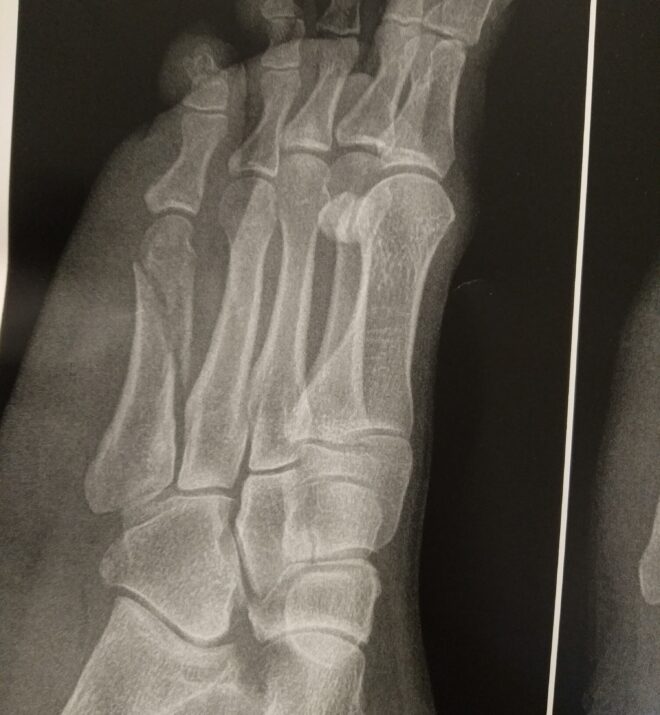

پرتوهای ایکس پا شکستگی مورب طولی شفت متاتارس پنج (شکل ۲ را ببینید) را نشان می دهند. اندازه قطعه شکستگی ممکن است بسیار متفاوت باشد.